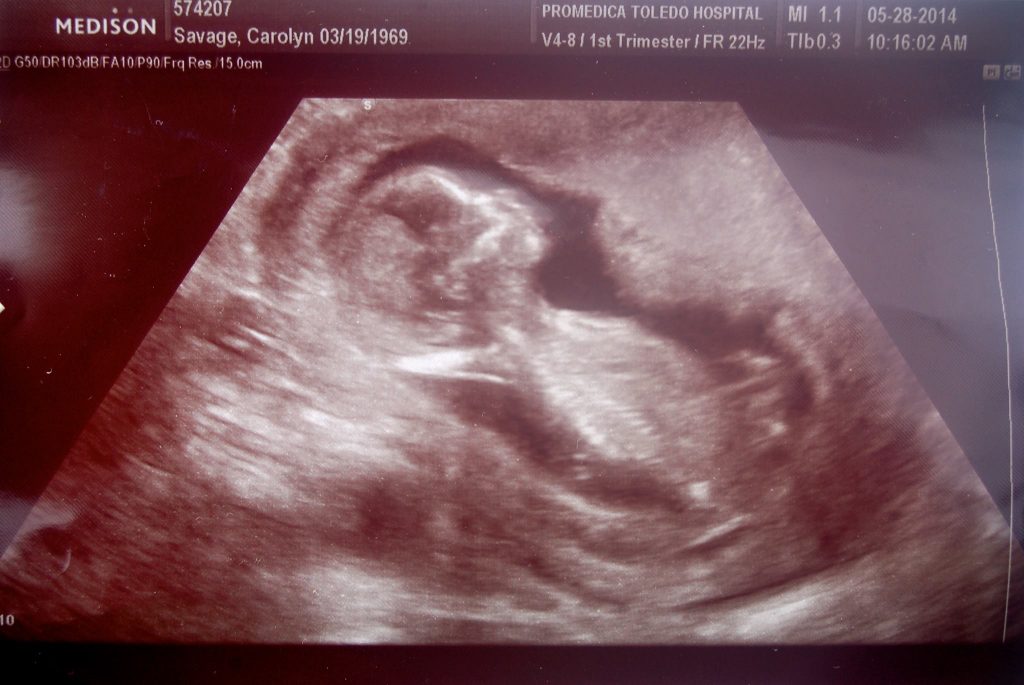

Paret fick ytterligare en överraskning 2014. Carolyn kunde inte tro sina ögon när hon tittade ner på graviditetstestet.

”Jag trodde inte det var sant. Jag var infertil. Jag har genomgått otaliga fertilitetsbehandlingar under de senaste två decennierna. Jag är 45 år. Är det verkligen sant?”

Nicholas Winton Savages föddes hösten 2014, och plötsligt bestod Carolyn och Sean Savages familj av 8 personer, trots deras fertilitet i två decennier.